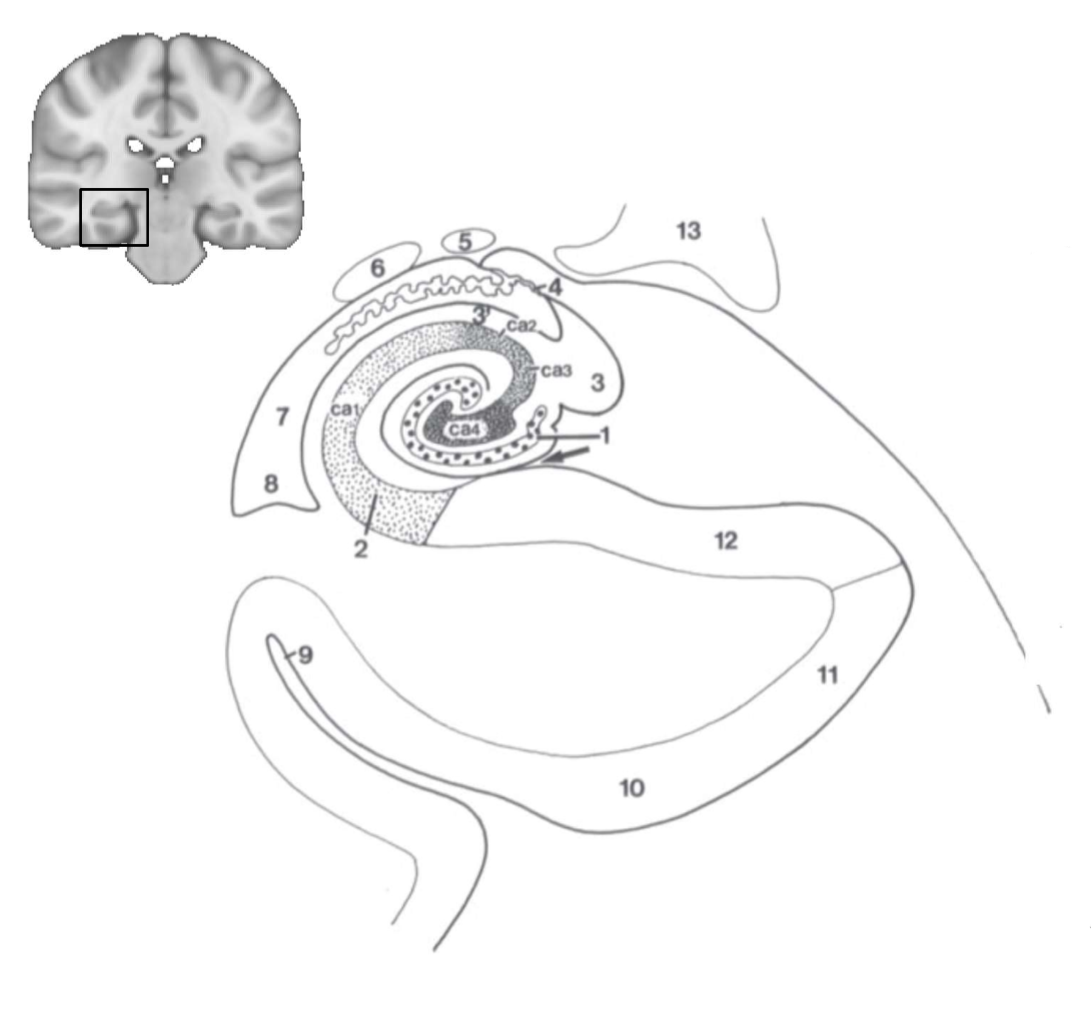

What structure is this?

hippocampus

What is 1?

hippocampus

What is 2?

rhinal sulcus

What is 3?

lateral ventricle

What is 4?

thalamus

What is 5?

entorhinal cortex

What is 6?

perirhinal cortex

What is 7?

parahippocampal cortex

What is 1?

gyrus dentatus

What is 2?

cornu ammonis

What is 3?

fimbria

What is 3’?

alveus

What is the arrow pointing to?

happicampal sulcus

What is ca1, ca2, ca3 and ca4?

fields of cornu ammonis

What is 4?

tela choroidea

What is 5?

stria terminalis

What is 6?

tail of caudate nucleus

What is 7?

temporal horn of lateral ventricle

What is 8?

collateral eminence

What is 9?

collateral sulcus

What is 10?

parahippocampal

What is 11?

entorhinal area

What is 12?

subiculum

What is 13?

lateral geniculate body